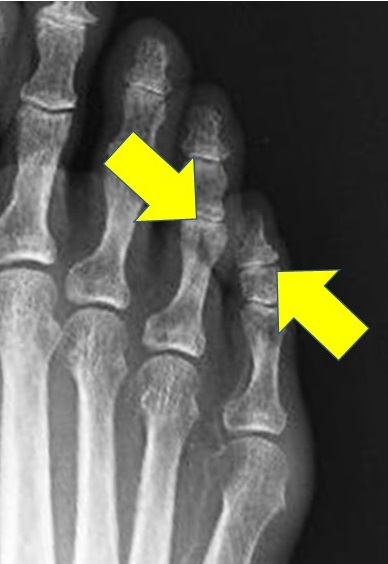

レントゲンで見るとその原因がよくわかります。ご覧のように第4趾の中節骨の張り出しと第5趾の末節骨の張り出しがちょうど当たる位置になってしまうと、骨と骨が当たってそこに痛い胼胝が出来るのです。